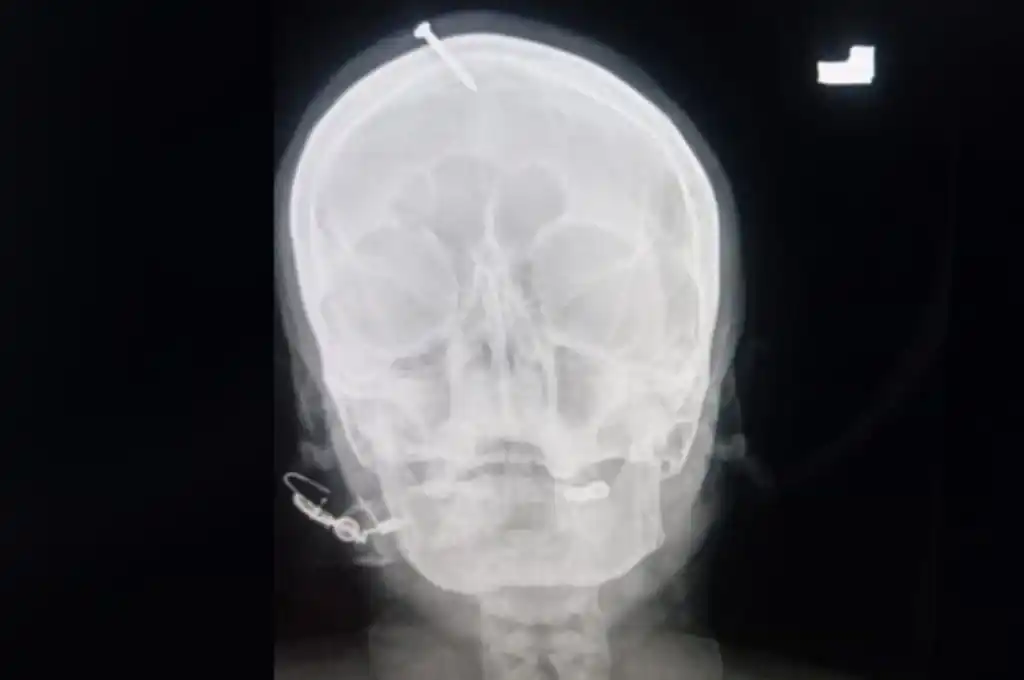

Una radiografía mostró que el clavo, de cinco centímetros, había perforado la frente de la mujer, pero sin alcanzar el cerebro.

Una radiografía mostró que el clavo, de cinco centímetros, había penetrado lo suficiente para perforar el hueso frontal de la mujer, pero sin alcanzar el cerebro. “Intentaron quitárselo en casa, pero no pudieron”, señaló Suleman.